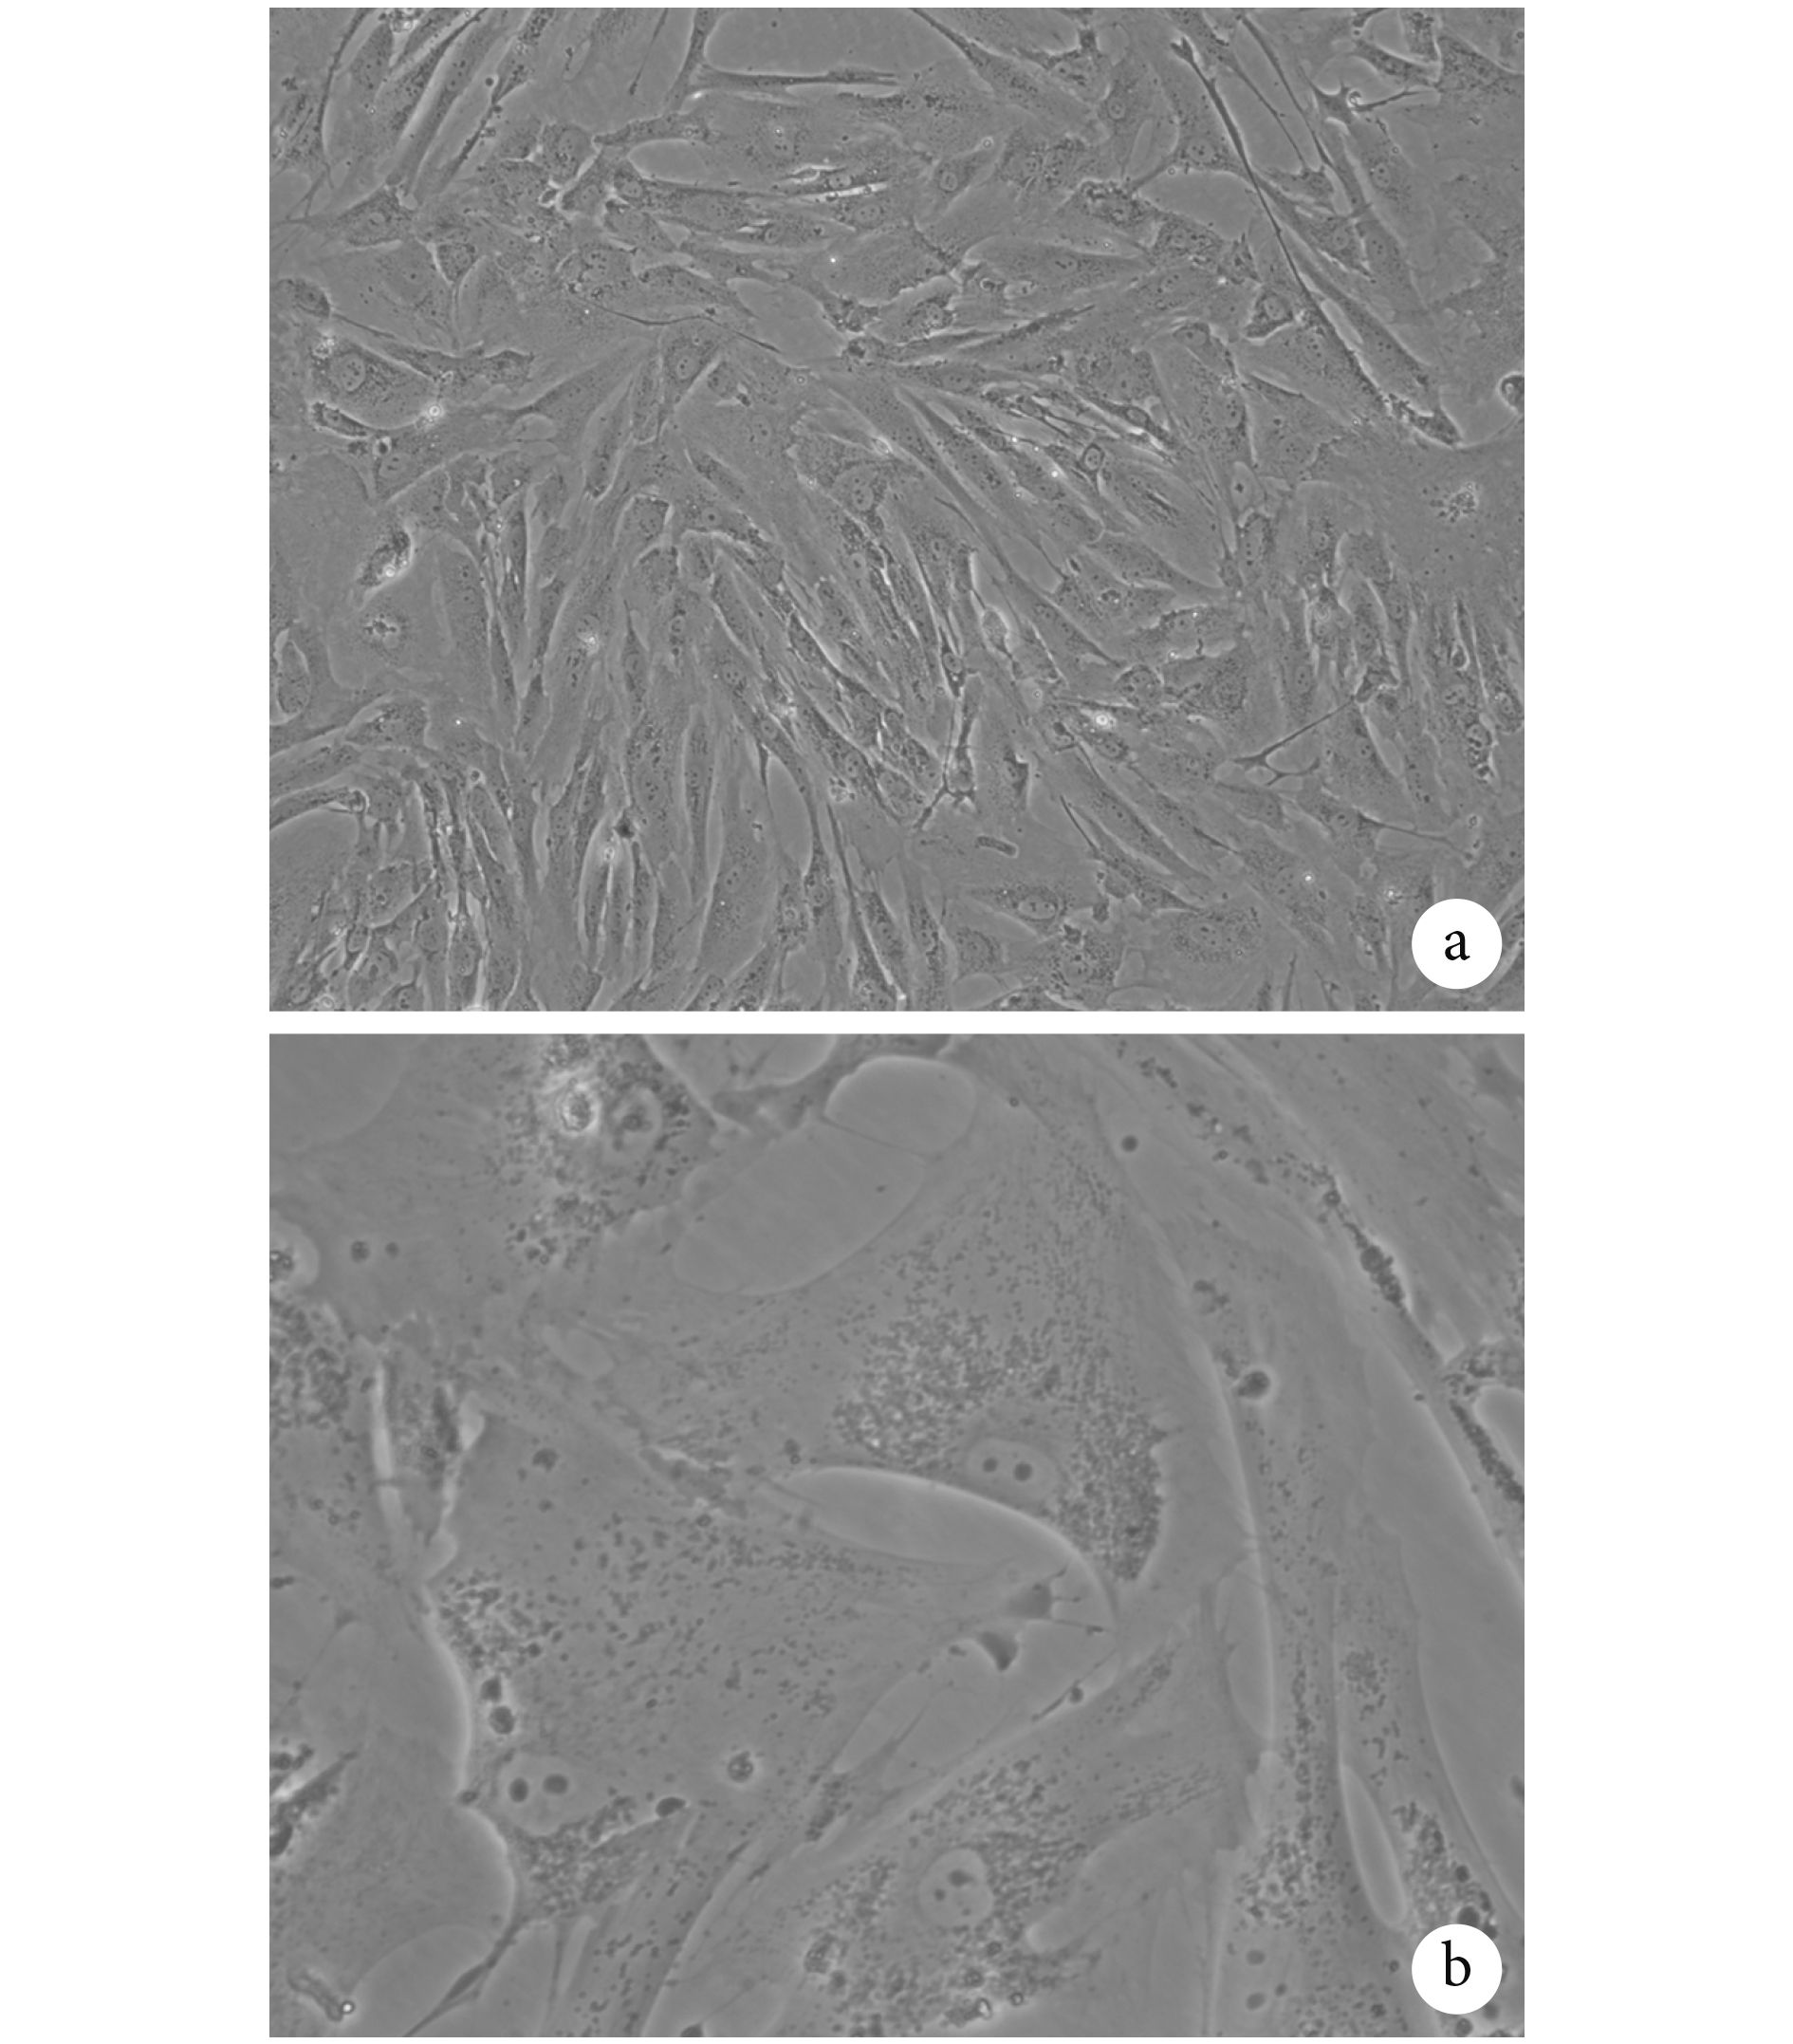

2.1 分離得到的 AVICs

用含 10% 胎牛血清的培養基培養分離得到的 AVICs,倒置顯微鏡下觀察細胞貼壁后呈現出狹長條形樣改變,主要表現為梭形和多角形(圖 1),該細胞生長較為緩慢,每 3 d 更換一次培養基,每 7~10 d 傳代。